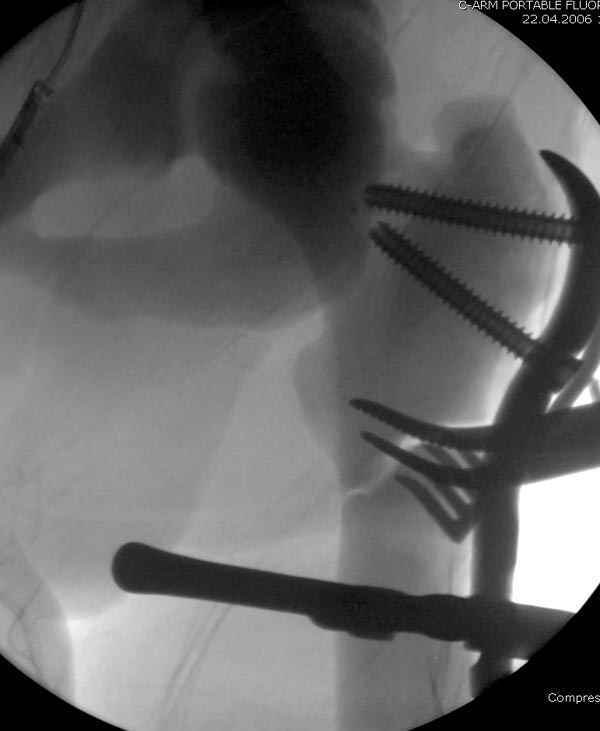

После неудачной попытки скелетного вытяжения в первом мед.учреждении, после осмотра снимков и изучения истории, поставили диагноз “Остеопетроз” или мраморная болезнь, редкая наследственная костная паталогия, где имеется нарушение формации остеокластов.

Конечно, было бы идеальным применение интрамедуллярного остеосинтеза, но учитывая прежний собственный опыт (лечил перелом бедра) и

публикации, предупреждающие о трудностях при обработке кости (иногда из-за неподготовленности инструментария результатом была неадекватная фиксация перелома, или перенос операции из-за фактора усталости оперирующего персонала), решили применить пластину (и в этом же случае был выбран Synthes plate, так что представитель за два дня

Заказаны были дополнительные различные дрели, и на следующий день, усиленной бригадой, больного прооперировали, потратив на каждое отверстие около 25-35 минут, хотя сверлили с охлаждением по нарастающей по диаметру сверл и с их заменой каждые 2 мм сверления.